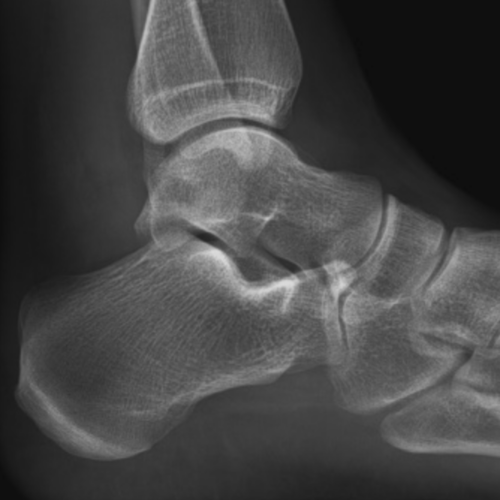

· Ham Clock looks great and is a real enrichment for every ham radio operator · RADIOGRAPHIE DE LA HANCHE DE FACE 4 juin 17 Dans "BANQUES D'IMAGES" RADIOGRAPHIE DU POIGNET DE FACE 4 juin 17 Dans "BANQUES D'IMAGES" Publié dans BANQUES D'IMAGES , Non classé , RADIOGRAPHIES Navigation des articles1) des radios en position debout FACE et PROFIL du pied EN ENTIER Elles permettent de mesurer les angles qui confirment la déformation en pied plat Le cliché de profil debout cherche à évaluer la divergence du talus et du calcaneum (ou inclinaison de l'astagale par rapport au calcaneum)

En effet, le pied étant un organe de la locomotricité (marche), l'analyse n'a d'intérêt que lorsqu'il est en appui Une radiographie du pied en charge nous permettra d'analyser précisément l'architecture de votre pied dans le cadre du bilan radiologiqueSearch query Yahoo Help;2,371 Free images of Radio Related Images microphone music sound audio retro technology headphones fireworks vintage radio 312 55 Radio Cassette Speaker 718 134 Car Traffic Man Hurry 409 63 Microphone Music Sound 310 90 Open Fire Fire Embers 131 162 Headphones Radio Music 167 31 Shower Of Sparks Light 130

· Les radiologues de centre d'imagerie IMBM, situé dans le quartier Batignolles Montmartre, dans le 18ème, réalisent votre radio de la cheville ou des pieds à ParisCet examen est réalisé en cas de douleurs, de traumatisme, de chute, de suspicion d'arthrose Nous réalisons les clichés conventionnels debout, de face, profil, avec les clichés en charge afin de réaliser lesPour une étude statique de vos pieds, les radiographies se réalisent debout, le pied sur le capteur Le profil de pied se réalise sur un marchepied spécifique Il vous faudra monter 3 marches et placer vos pieds de part et d'autre d'une gouttière où sera placé le capteur WIFI · Pour prendre une photo en projection directe (plantaire arrière) le pied est placé sur la semelle en position couchée, les jambes pliées au niveau des genoux Une image de chaque doigt sur le côté est réalisée avec la pose latérale du pied et